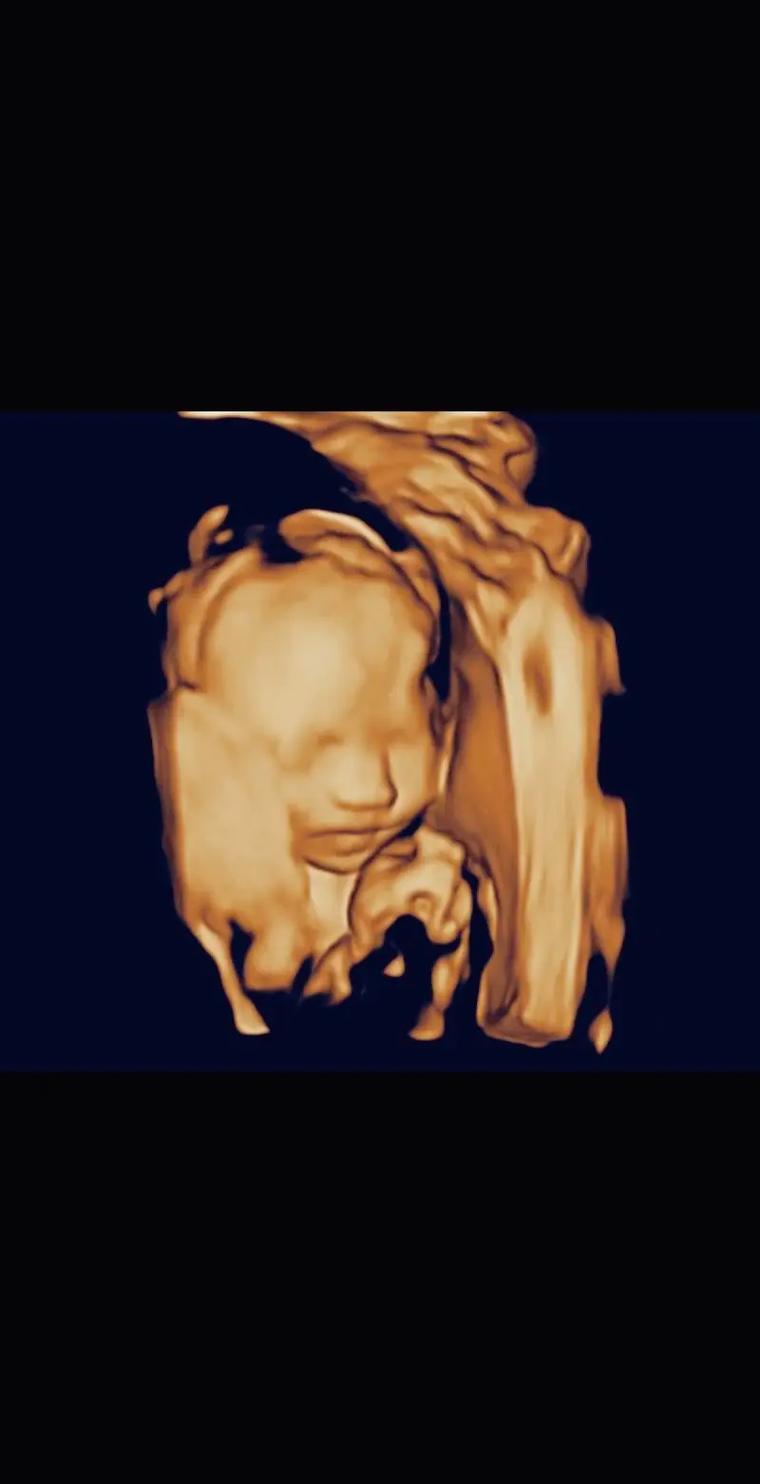

四维彩超下的试管宝宝:亲身经历分享

分享一位试管婴儿准妈妈的四维彩超检查经历,以及对试管婴儿过程的感悟和期待。

四维彩超是一种超声检查技术,它在传统三维超声的基础上增加了时间维度参数,能够实时获取胎儿或人体内部器官的动态立体图像。通过它,医生可以清晰观察胎儿的生长发育情况,如面部表情、肢体动作等,也可用于检查腹部脏器等。例如在孕期检查中,能排查胎儿是否存在结构畸形,让准父母提前看到宝宝模样。